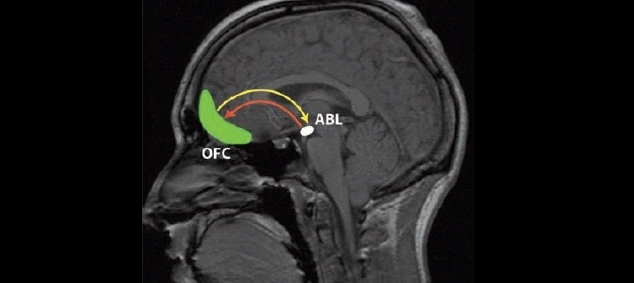

În cadrul unui joc de investiţii efectuat în laborator, trei femei ce suferiseră vătămări într-o parte a creierului cunoscută sub numele de basolateral amygdala (ABL) cedau de două ori mai mulţi bani unor străini în comparaţie cu oamenii sănătoşi.

Oamenii de ştiinţă susţin că rezultatele studiului sugerează că atunci când funcţionează normal, amigdala bazolaterală joacă un rol important în activarea egoismului – inhibând astfel generozitatea.